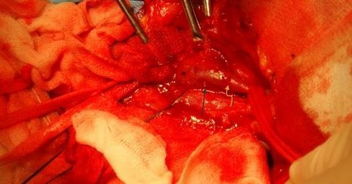

诊断:右颈部包块 治疗;于次日局麻下行 “右 颈部包块探查取出术 ” 。 2% 利多卡因包块区局麻浸 润下 , 于右胸锁乳突肌中 1 /3处该肌后缘, 沿“包块 ”走形 , 向后下切开长 约 1 cm的皮肤切口, 分离其下皮下组织, 即暴露出其上端 (较粗 ), 见是一白色 鱼 刺 , 用血管钳夹住其上端头部, 顺利拔除一长约3. 0 cm× 0. 2 cm× 0. 1 cm光滑的鱼 刺 , 缝 合切 口。术后 第 1天 , 换药时几乎无疼痛 。追问病史 : 患者半年前 吃鱼时 , 曾有被鱼刺卡住右咽喉史, 偶有吞咽进食疼痛及异物感,之后咽 异物感消退 , 而未引起 重视。术后7d拆 线,切口 愈合 好 。